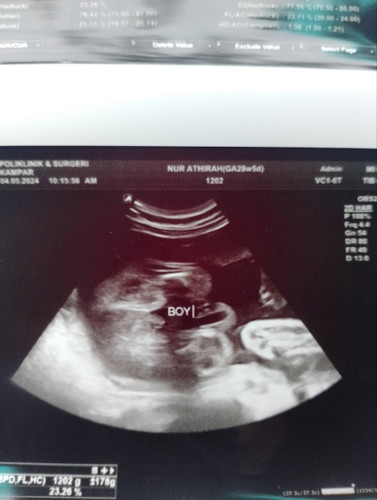

hi mommies ! nak tanya ni , kalau mommies diluar sana lebih percayakan scan di klinik swasta or kerajaan ? sebab saya scan kat kk dorang cakap baby girl , tapi bila buat detail scan kat swasta dorang cakap boy ! mana satu ye ? nak beli barang baby pun ragu ii ni , btw ni gambar scan kat swasta tu 😅#SeriusTanya #bantujawab #ingintahu #bantusharing #Sharing_dong_Bund

Biasa scan kk tak jelas. Tapi nmpk jelas dah tu boy

Kalu tngok mmg boy ni sis🤭

jelas nampak baby boy